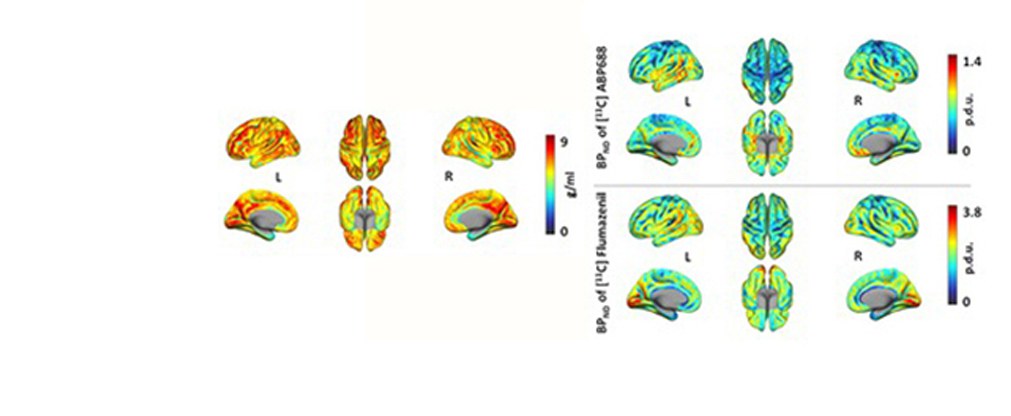

Die Forschungs- und Entwicklungsarbeiten unserer Institutsbereiche der Physik der Medizinischen Bildgebung (INM-4) des Instituts für Neurowissenschaften konzentrieren sich auf die Entwicklung, experimentelle Validierung und klinische Prüfung neuer Bildgebungsmethoden des Gehirns.

Jülicher Bildgebungstechnik ermöglicht präzise Einblicke in Struktur und Funktion des menschlichen Gehirn

6.Juli 2024 - Bewertung von Abschwächungskorrekturmethoden für die PET/MR-Bildgebung

5. April 2024 - Neue Studie zeigt verbesserte Totzeitkorrektur bei der PET-Gehirnbildgebung

15. Februar 2024 - KI-gestützte PET-Bildgebung identifiziert verborgene Hirntumorläsion